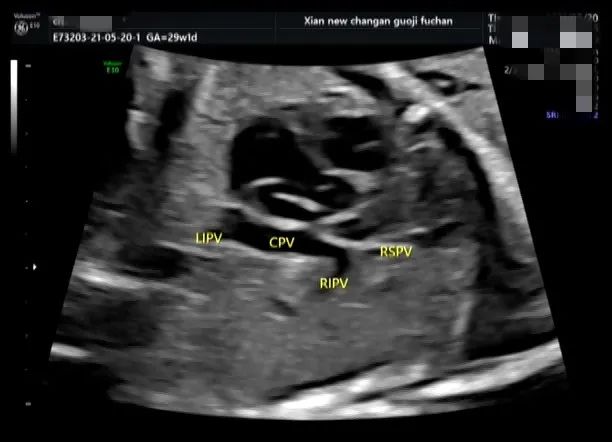

完全性肺静脉异位引流

XXX 女 48 岁 G1PO 孕 29W1D 既往无不良孕史

外院系统、四维超声未发现心脏显著异常,心脏超声检查时发现左心系统小,瓣环及主动脉峡部略细,肺静脉异位引流待排。为进一步明确诊断,特来我院请张军教授会诊。我科行胎心检查时发现左房内未见肺静脉开口;四只肺静脉在左房后方形成共同静脉干后向下走形进入肝静脉。遂做出完全性肺静脉异位引流(心下型)的诊断,为了解生后手术情况,患者到上级医院会诊,证实了此诊断。

正常情况下,四支肺静脉均应引流入左心房。完全性肺静脉异位引流指四条肺静脉形成共同肺静脉干,未引流入左心房,而通过不同途径引流入右心房,右心房内的动静脉混合血一部分经三尖瓣入右心室、肺动脉,一部分经房间隔缺损引流入左心房供应体循环。

TAPVC 发病率低、畸形复杂,诊断相对困难。因存在大量右向左分流,所以新生儿期即出现紫绀、呼吸困难等缺氧症状,情况危急,需早期手术。如果在产前能做出明确诊断,有利于生后做好相应处理措施。